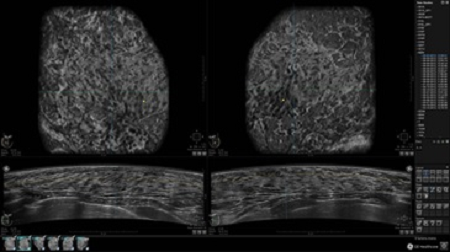

• Отображение объемных 3D ультразвуковых изображений, которые состоят из традиционных поперечных и воссозданных коронарных и сагиттальных проекций

• Возможность отображения полного 3D изображения

• Многооконный просмотр: 4 - 12 изображений

• Стандартизованная ориентация изображения: «толстый срез» в коронарной плоскости; поперечная; сагиттальная плоскость; радиальный и антирадиальный поворот изображения; просмотр исключительно области интереса

• Изменяемая толщина среза: 0,5 - 10,0 мм (шаг 0,5 мм)

• Срез: 0,5 - 2,0 мм (шаг 0,5 мм)

• Одновременный просмотр двух изображений для сопоставления в коронарной плоскости